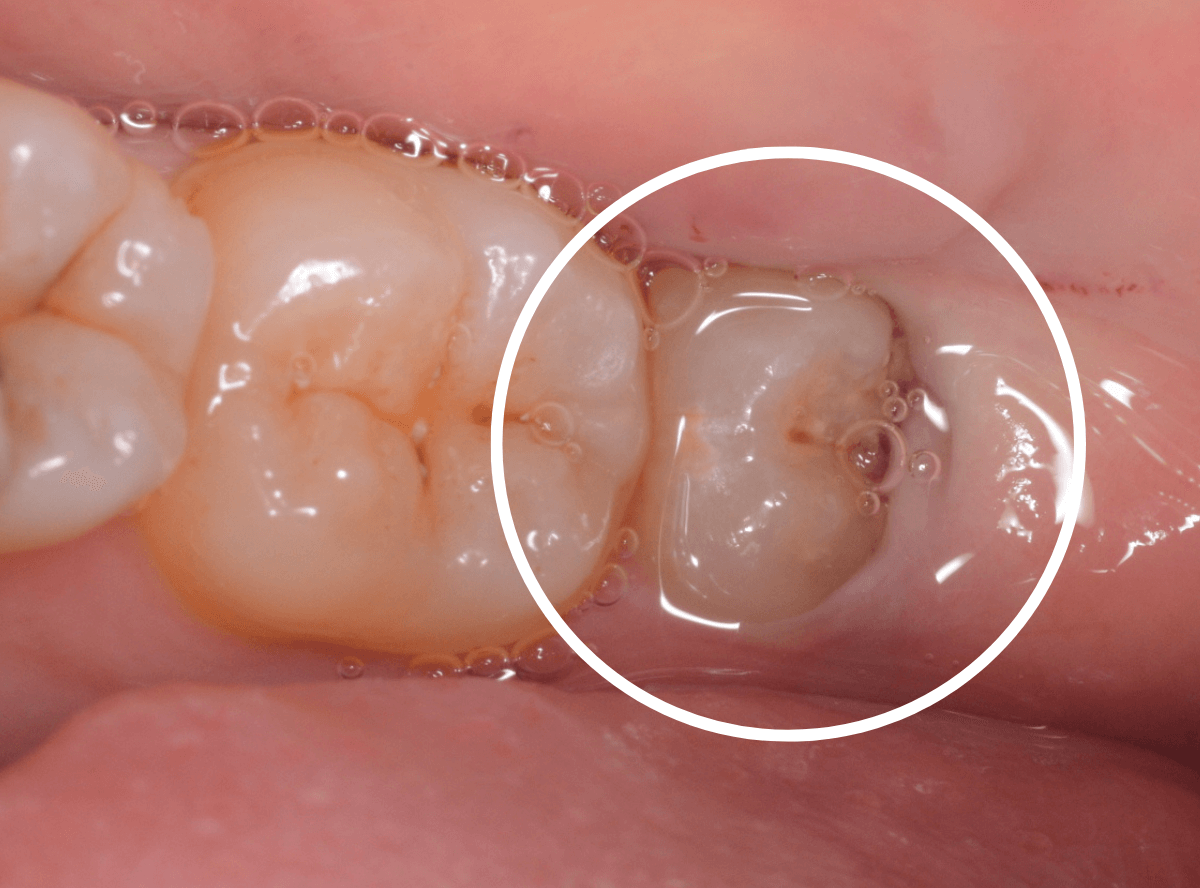

ここでは、比較的簡単なおやしらずの抜歯の例を中心にご紹介します。

このようなおやしらず、あなたはありませんか?